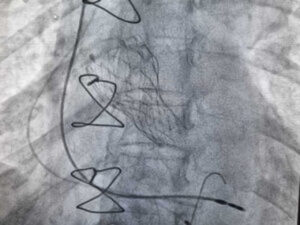

छत्तीसगढ़ निवासी उम्र के छठवें दशक के मध्य की महिला मरीज की 2010 में निजी अस्पताल में ओपन हार्ट सर्जरी हुई थी जिसमें हृदय के दो वाल्व चेंज हुए थे। 2017 में पुनः ओपन हार्ट सर्जरी हुई जिसमें दो वाल्व और चेंज हुए। इसके बाद मरीज की 2017 में हुई सर्जरी की जटिलता के कारण जनित धड़कन की कमी के चलते 15-20 दिन के बाद पेसमेकर लगाने के लिए फिर सर्जरी हुई। इन तीन सर्जरी के बाद मरीज का हार्ट पम्पिंग काफी कम हो गई थी। अगले कुछ सालो में पुराने सर्जिकल वाल्व भी धीरे धीरे खराब हो गए। मरीज को दोनों सर्जरी द्वारा प्रतिरोपित वाल्व में अत्यधिक सिकुड़न होने के कारण साँस लेना कठिन होता जा रहा था । टिश्यू वाले वाल्व में खराबी और सिकुड़न जल्दी आ जाते हैं। इसके बाद मरीज को एडवांस कार्डियक इंस्टीट्यूट के कार्डियोलॉजी विभाग में आगे उपचार के लिए आकलन और परियोजना बनाई गई। इस जटिल कार्डियक प्रक्रिया करने की योजना बनाने के लिए डॉ भीमराव आंबेडकर हॉस्पिटल के रेडियोडायग्नोसिस विभाग से डॉ. एस. बी. एस. नेताम ने सी टी कोरोनरी एंजियोग्राफी द्वारा वाल्व का सटीक माप निर्धारित करके दिया और निश्चेतना विशेषज्ञ डॉ. शशांक ने मरीज़ को बिना बेहोश किए पूरी प्रक्रिया के दौरान अर्धचेतन अवस्था में संभाले रखा। टेक्निकल टीम का नेतृत्व खेम सिंह और जीतेन्द्र चेलकर और कैथ लैब में मुख्य नर्सिंग असिस्टेंट आनंद सिंह ने मरीज़ के ब्लड प्रेशर और धड़कन को मॉनिटर किय। डॉ प्रतिक गुप्ता ने प्रक्रिया के दौरान इकोकार्डियोग्राफी द्वारा वाल्व की स्थिति निरंतर दिखाई।

डॉ. स्मित श्रीवास्तव के अनुसार दो वाल्व की एक साथ प्रक्रिया करना जोखिम को कई गुना बढ़ा दिया था , साथ ही पुराने पेसमेकर का एक तार खराब हुए वाल्व के बीच में था जिसके प्रकिया के दौरान मरीज की धड़कन के बंद होने की सम्भावना का कारण बन सकता था। मरीज का हार्ट कम पम्प कर रहा था इसलिए दवाओं के सहारे हार्ट की पम्पिंग क्षमता को ठीक किया और बिना छाती खोले हार्ट के बाएं तरफ के ऐऑर्टिक वाल्व का टावी प्रोसीजर के जरिए वाल्व चेंज करने का निर्णय लिया। इसके साथ ही साथ दाहिने तरफ के ख़राब ट्राइकस्पिड वाल्व को भी खोलने का निर्णय लिया। हार्ट के बाएं हिस्से में स्थित पुरानी 2010 की सर्जरी द्वारा लगाए गए एओर्टिक वाल्व के अंदर ही जांघ की नासिका के रास्ते बिना छाती खोले नया वाल्व लगाया जिसे सेल्फ एक्सपेंडिंग वाल्व कहते हैं। इस वाल्व को पुराने वाल्व से थोड़ा ऊपर खोला जिसके कारण मरीज के खून का बहाव काफी अच्छा हो गया। इस वाल्व को लगाने के बाद मरीज की सांस फूलने और अन्य दूसरी गंभीर दिक्कतें दूर हो गई। मरीज का जीवन पहले की तुलना में बेहतर हो गया। डॉ. स्मित श्रीवास्तव के अनुसार दिल के दाहिने हिस्से में पुरानी 2017 की सर्जरी द्वारा लगाए गए संकीर्ण और ख़राब हो चुके पुराने ट्राइकस्पिड वाल्व को भी बिना छाती खोले दायें गर्दन की नस जुगलर वेन के माध्यम से बैलून की सहायता से खोल दिया गया। उपचार प्रक्रिया के बाद पुराना पेसमेकर यथावत अपना काम कर रहा है और मरीज़ पूर्ण स्वस्थ होने की राह पर है।